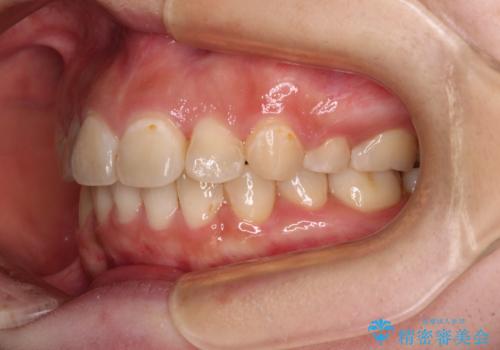

- 前歯の著しいデコボコを気にして来院された患者様です。

上顎の左右側切歯(前から2番目)が裏側に隠れいてる状態で、咬み合わせや清掃性に大きな問題が認められました。

左下に八重歯があったそうですが、当時は矯正治療を行うことを考えていなかったため、抜歯してしまったとのことでした。

叢生が著しいため、左下以外の第一小臼歯3本を抜去し、目立たないワイヤー装置にて矯正治療を行うこととしました。

これほど顕著に裏側に隠れいてる歯ですと、仕上がったときに両隣の歯と軸に差が認められることが多いのですが、殆ど違和感のない歯並びを達成することができました。